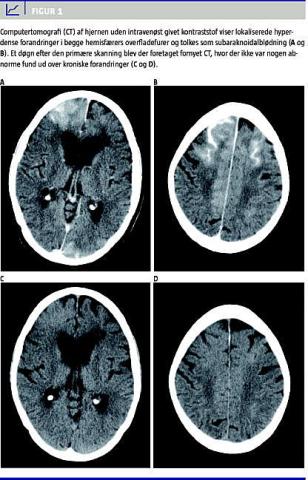

Under og efter proceduren fik patienten motorisk uro, konfusion og nedsat kraft af venstre overekstremitet og forhøjet blodtryk på 210/110 mmHg. Fire timer efter proceduren blev der på mistanke om intracerebral blødning udført akut computertomografi (CT) af cerebrum (CTC) uden brug af intravenøst (i.v.) givet kontraststof (Figur 1 ). Skanningen viste lokaliserede hyperdense forandringer i hjernens overfladefurer i begge hemisfærer samt universelt ødem og blev derfor tolket som en stor SAH. På trods af at det var tale om en tom skanning, var der tydelig kontrastopladning i hjernens kar, hvilket dog ikke blev identificeret primært. Acetylsalicylsyre og clopidogrel blev pauseret, og patienten blev observeret tæt. Inden for samme døgn aftog symptomerne, og der blev udført fornyet CTC uden i.v. kontrast 26 timer efter KAG/PCI. Denne skanning viste ingen tegn på SAH, ødem eller iskæmi, og der blev ikke fundet noget abnormt ud over kroniske forandringer i form af atrofi og leukoariose. Patienten blev udskrevet to døgn senere i habituel tilstand.